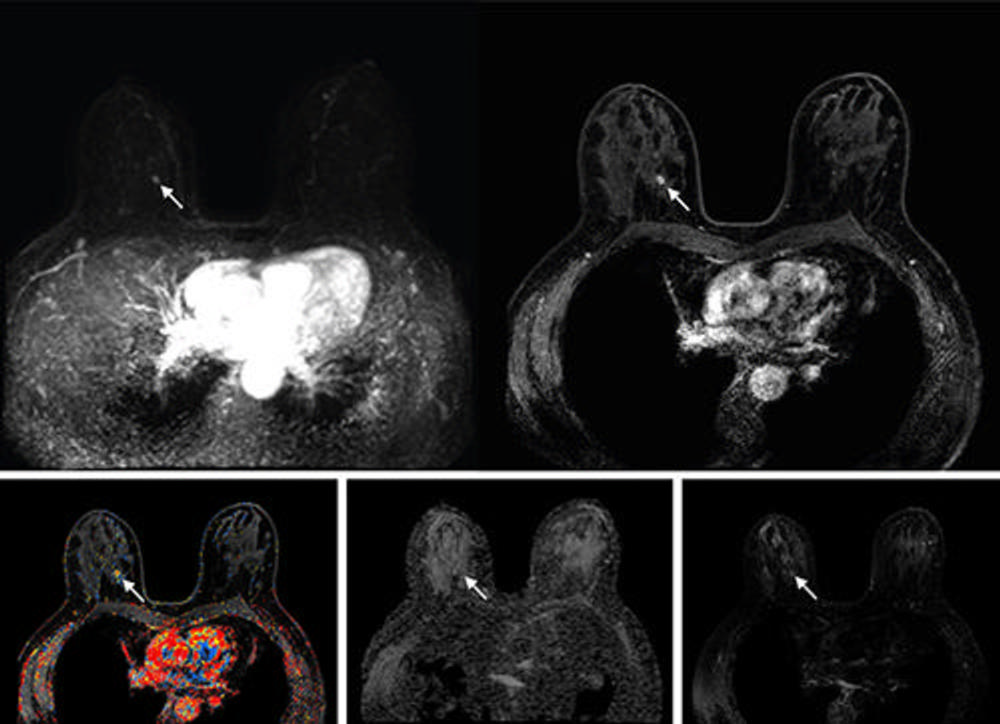

Figure 5. Abbreviated axial MRI images show a 7-mm irregular mass with irregular margin (arrows) in the right upper inner quadrant with early rapid enhancement (Breast Imaging Reporting and Data System category 4 [suspicious for cancer]). The participant was recalled and underwent an MRI-guided vacuum-assisted biopsy that showed sclerosing adenosis with microcalcifications and usual ductal hyperplasia and focal apocrine metaplasia. On the full-protocol images (not shown), the lesion was T2-weighted hypointense and showed diffusion restriction and washout kinetics in the delayed phase, characteristics that would not have reversed the decision to recall the participant.

High-res (TIF) version